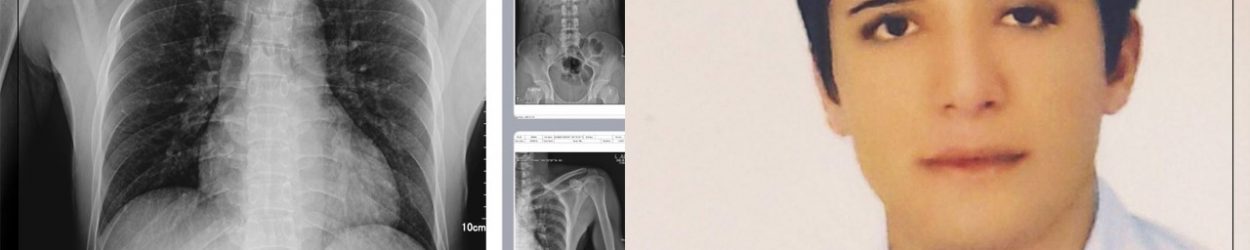

سیروان محمدی، جوانی که دو ماه پیش پس از شکنجه شدید و شکستگی چند ناحیه بدن از بازداشتگاه اداره اطلاعات سنندج آزاد شده بود؛ بار دیگر توسط نیروهای این اداره با یورش مسلحانه در منزل ربوده شد که در جریان این ربایش پدر و برادر او نیز زخمی شدند.

سیروان محمدی، طی دوره بازداشت قبلی خود در اداره اطلاعات سنندج بر اثر شکنجه شدید دچار شکستی از ناحیه، جمجمه، بینی، گوش و سه دنده قفسه سینه شد.

این شهروند در روز چهارشنبه ٢۵ آبان ١۴٠١ در سنندج، توسط نیرو‌های حکومتی ربوده و به قرارگاه شهرامفر منتقل شد. وی نهایتاً در روز شنبه ١٧ آذر ماه ١۴٠١، پس نزدیک به یک ماه شکنجه و بازجویی به صورت موقت تا پایان مراحل دادرسی آزاد شده بود.